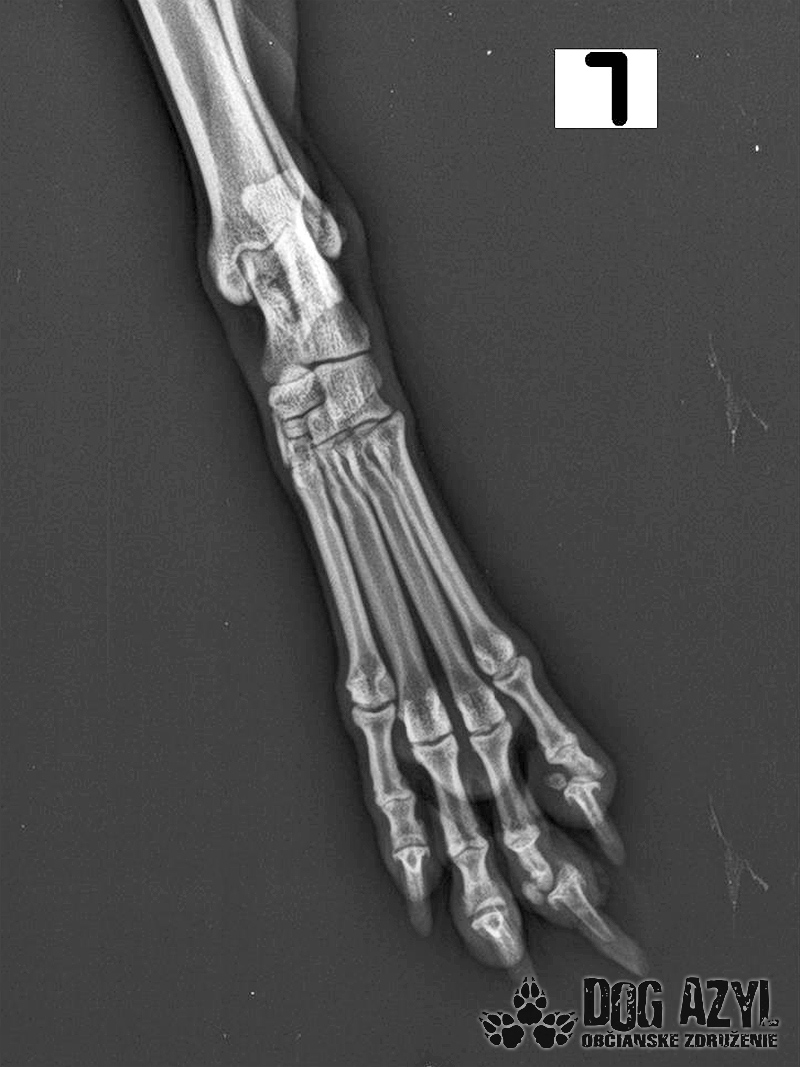

Mia, narodená máj 2015, sa našla zrazená v obci Bodza. Mala obrovské šťastie, že ju nálezkyňa ihneď naložila do auta a utekala s ňou k nášmu veterinárovi. Bola v katastrofálnom stave a mala obrovské bolesti :( Keďže Mia bola čipovaná, hneď sme sa dopátrali aj k majiteľom, ale na druhej strane telefónu nám bolo oznámené, že Miu darovali niekomu ale nemajú kontakt. Tak sme trocha pátrali a vypátrali sme, že Mia bola darovaná "do dobrých rúk" z postele priamo na dvor! Rodina sa tvárila veľmi zodpovedne a láskyplno, ale zrejme nepochopili,že Mia je kastrovaná a už nebude produkovať šteniatka. Po pár neúspešných pokus spáriť ju so samcom putovala do ďalších dobrých rúk" a to k miestnemu alkoholikovi, kde skončila v šope na reťazi a spala na kope hnoja :( Podarilo sa jej nejakým zázrakom ujsť, ale žiaľ skončila pod kolesami auta. Čomu sa vlastne ani nečudujeme, keďže cez tie zlepené chlpy nemala najmenšiu šancu vidieť pred seba. Mia podstúpila veľmi náročnú operáciu panvy, ktorá sa úspešne podarila, ale pri chladnejšom počasí zvykne trocha krívať. Mala tiež zlomený pst na zadnej nohe, ktorý sa zle zrástol a tak jej nechtík rastie trocha krivo a treba ho pravidelne strihať. Vôbec nič jej to však neuberá na kráse a chuti do života :) Mia si hľadá rodinu, ktorá jej vie sľúbiť, že ju nikdy viac neopustí. Je to skôr pokojná fenka, nie je vôbec náročná na pohyb ale na maznanie o to viac :) Veľmi rada sa túli k človeku, je veľmi priateľská a kontaktná. Vôbec jej nevadí spoločnosť iných psíkov ani mačiek ale nepotrebuje ich ku svojej spokojnosti :) Mia je dokonale vhodná do bytu, ale k malým deťom určite nie, má totiž rada svoje súkromie. Ak by sa mala adoptovať k rodinnému domu tak podmienkou je bývanie v dome.